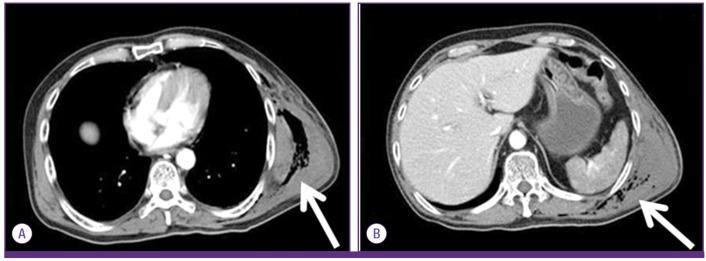

Most cases of gas gangrene caused by Clostridium species begin with trauma-related injuries but in rare cases, spontaneous gas gangrene (SGG) can occur when patients have conditions such as advanced malignancy, diabetes, or immunosuppression. Clostridium perfringens, a rare cause of SGG, exists as normal flora of skin and intestines of human. Adequate antibiotics with surgical debridement of infected tissue is the only curative therapeutic management. Mortality rate among adults is reported range of 67-100% and majority of deaths are occurred within 24 hours of onset. We experienced a case of SGG on the trunk, buttock and thigh in a neutropenic patient with acute lymphoblastic leukemia. His clinical course was rapid and fatal during pre-engraftment neutropenic period of allogeneic stem cell transplantation.

大多数由梭菌属引起的气性坏疽病例始于与创伤相关的损伤,但在罕见情况下,当患者患有晚期恶性肿瘤、糖尿病或免疫抑制等疾病时,可发生自发性气性坏疽(SGG)。产气荚膜梭菌是SGG的罕见病因,存在于人类皮肤和肠道的正常菌群中。使用足够的抗生素并对感染组织进行手术清创是唯一的治愈性治疗方法。据报道,成人死亡率在67%至100%之间,大多数死亡发生在发病后24小时内。我们遇到一例急性淋巴细胞白血病中性粒细胞减少患者,其躯干、臀部和大腿发生了SGG。在异基因干细胞移植的植入前中性粒细胞减少期,他的临床病程迅速且致命。